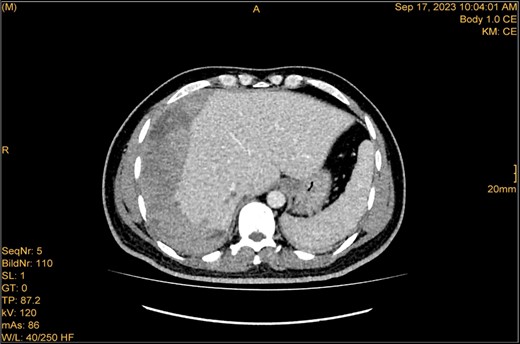

A 41-year-old male with a clear medical background, presented to the Emergency Department with right upper quadrant (RUQ) abdominal pain for two days, associated with fatty dyspepsia, anorexia, nausea, and vomiting. On arrival, his heart rate was 111 bpm with a blood pressure of 128/94 mmHg. On examination, a yellowish discoloration of skin and sclera was noted with a negative murphy sign. Investigations showed elevated liver enzymes (LFT). An initial abdominal ultrasound showed a distended gallbladder with a thickened wall and multiple stones, largest measuring approximately 1.4 cm, and a common bile duct measuring 5 mm (Fig. 1). A magnetic resonance cholangiopancreatography (MRCP) identified a tiny 4-mm mid-cystic duct stone without intrahepatic biliary dilatation. After the initial management, an emergency LC was performed, which posed minimal challenges. Fortunately, no intraoperative complications were reported. A drain was kept in the subhepatic area, and the patient was kept under close observation. Second day postoperatively, the patient experienced dizziness and an intense RUQ pain despite proper analgesia. His heart rate was 89 bpm with a blood pressure of 107/64 mmHg. Investigations showed a drop in hemoglobin level from 13.8 to 9.9 g/dl. An abdominal ultrasound showed a right subcapsular heterogeneous collection with a scalloped liver surface (Fig. 2). Therefore, an initial diagnosis of ISH post-LC was considered. Following the initial fluid resuscitation and blood transfusion, a further decline in hemoglobin level was noted reaching 8.8 g/dl. Further blood transfusion was commenced achieving stabilization. Further CT scan showed subcapsular hepatic hematoma measuring 7.1 × 19 × 21 cm, in its transverse, anteroposterior, and craniocaudal diameters, respectively, with no evidence of active extravasation (Fig. 3) confirming the final diagnosis of ISH post-LC. A multidisciplinary decision was made to continue conservative management after a proper explanation of the potential risk of sudden rupture of hematoma. The patient’s clinical condition and hemoglobin level, in addition to drain output, were meticulously monitored in the general ward, ensuring early detection of deterioration. Four days later, a follow-up CT scan revealed no new significant interval changes (Fig. 4). Nine days postoperatively, the patient was discharged with a follow-up appointment, which showed almost complete resolution.

Enhanced CT scan utilizing bleeding protocol. Status post-LC identified significant ISH with internal hyperdensity measuring 7.1 × 19 × 21 cm, in its transverse, anteroposterior, and craniocaudal diameters, respectively. Adjacent hyperemic liver parenchyma with intraparenchymal hematoma noted at segment 5, measured 4.7 × 4 × 4.7 cm. Intraparenchymal hypodensities noted at segments 8 and 4b, likely represent hepatic contusions and lacerations. No evidence of active contrast extravasation.

The study was done utilizing monophasic porto venous phase demonstrating intact vasculature. Relatively stable significant subcapsular and intraparenchymal hepatic hematoma with underlying parenchymal contusion and laceration. The study appears unremarkable with no new significant interval change.